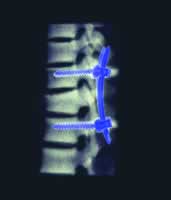

Iso-C 术中即时三维导航在脊柱外科的应用

脊柱外科手术近年得到了很大的发展,但是由于脊椎手术本身特点及脊柱的结构复杂,手术难度和危险性很高。许多手术需要进行复杂的立体操作,这些操作在非可视的情况下进入脊柱的腹地,会进一步增加手术的风险性,如椎弓根固定、寰枢椎关节间固定(Magerl术)及经后路椎体截骨矫形等。因此,更可靠、更安全的智能技术成为大家追求的目标并逐渐变为现实。智能手术首先变为实用技术的是计算机导航系统。随着该技术的逐步发展完善,已显示出精确定位的明显优点,提高了手术的安全性,并且术中X线照射量大大减少。因此越来越多的脊柱外科医师认可并接受了该项技术。

现代脊柱外科计算机导航系统主要使用的是红外线光学导航,该系统分辨率高,可以三维定位,不受手术室内其他设备的干扰 ......